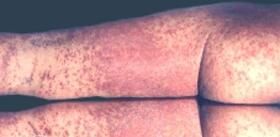

急性湿疹以密集的丘疹、丘疱疹为主,严重时出现小水疱,奇痒,搔抓后皮肤有渗出、糜烂。

急性湿疹经治疗后或炎症减轻之后,是亚急性湿疹,这时,红肿及渗出减轻,有少量丘疱疹,附以鳞屑和痂皮。

若治疗不当或反复发作,湿疹就会成为慢性,这时,皮肤呈慢性炎症,患部皮肤增厚,表面粗糙,上附鳞屑、结痂,损害多为局限性,边缘清楚,外周可出丘疹、丘疱疹,出现阵发性瘙痒。